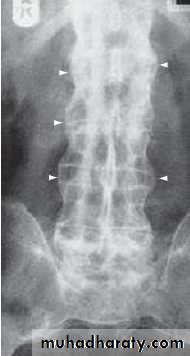

In advanced disease, ossification of the anterior longitudinal ligament and facet joint fusion may also be visible. The combination of these features may result in the typical ‘bamboo’ spine.

Radiographic changes in spondyloarthritis. A Fine symmetrical marginal syndesmophytes typical of ankylosing spondylitis (arrow).

B Coarse, asymmetrical non-marginal syndesmophytes typical of psoriatic spondylitis (arrow).

‘Bamboo’ spine of advanced ankylosing spondylitis. Note the symmetrical marginal syndesmophytes (arrows), sacroiliac joint fusion and generalised osteopenia